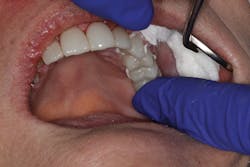

In the first case, a tooth with a subgingival margin preparation has been cleaned with an ultrasonic scaler and is gently dried in preparation for cementation. Note how the margin goes deeper subgingivally on the distolingual (figure 1). With TheraCem, a clean, prepped dentin or enamel surface is all that is needed to achieve excellent bond strengths, with the added benefit of sustained calcium and fluoride release. While TheraCem forms a strong bond to most substrates, including zirconia, a zirconia primer is still used prior to try-in to achieve optimal bond strength and prevent salivary contamination of the zirconia surface (figure 2).

Figure 2: Z-Prime Plus single-component priming agent